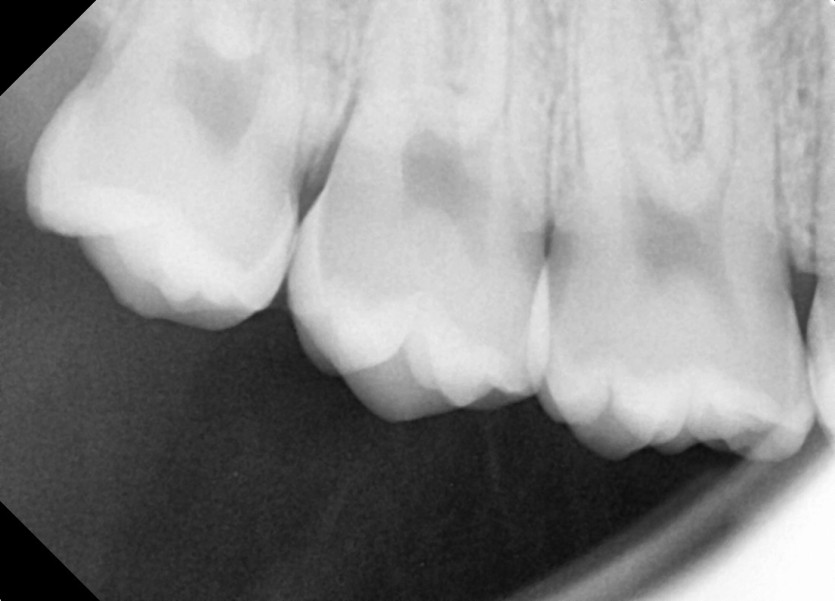

#18,28,38,48 사랑니 발치

구강 외과 전문의가 당일 발치했습니다.